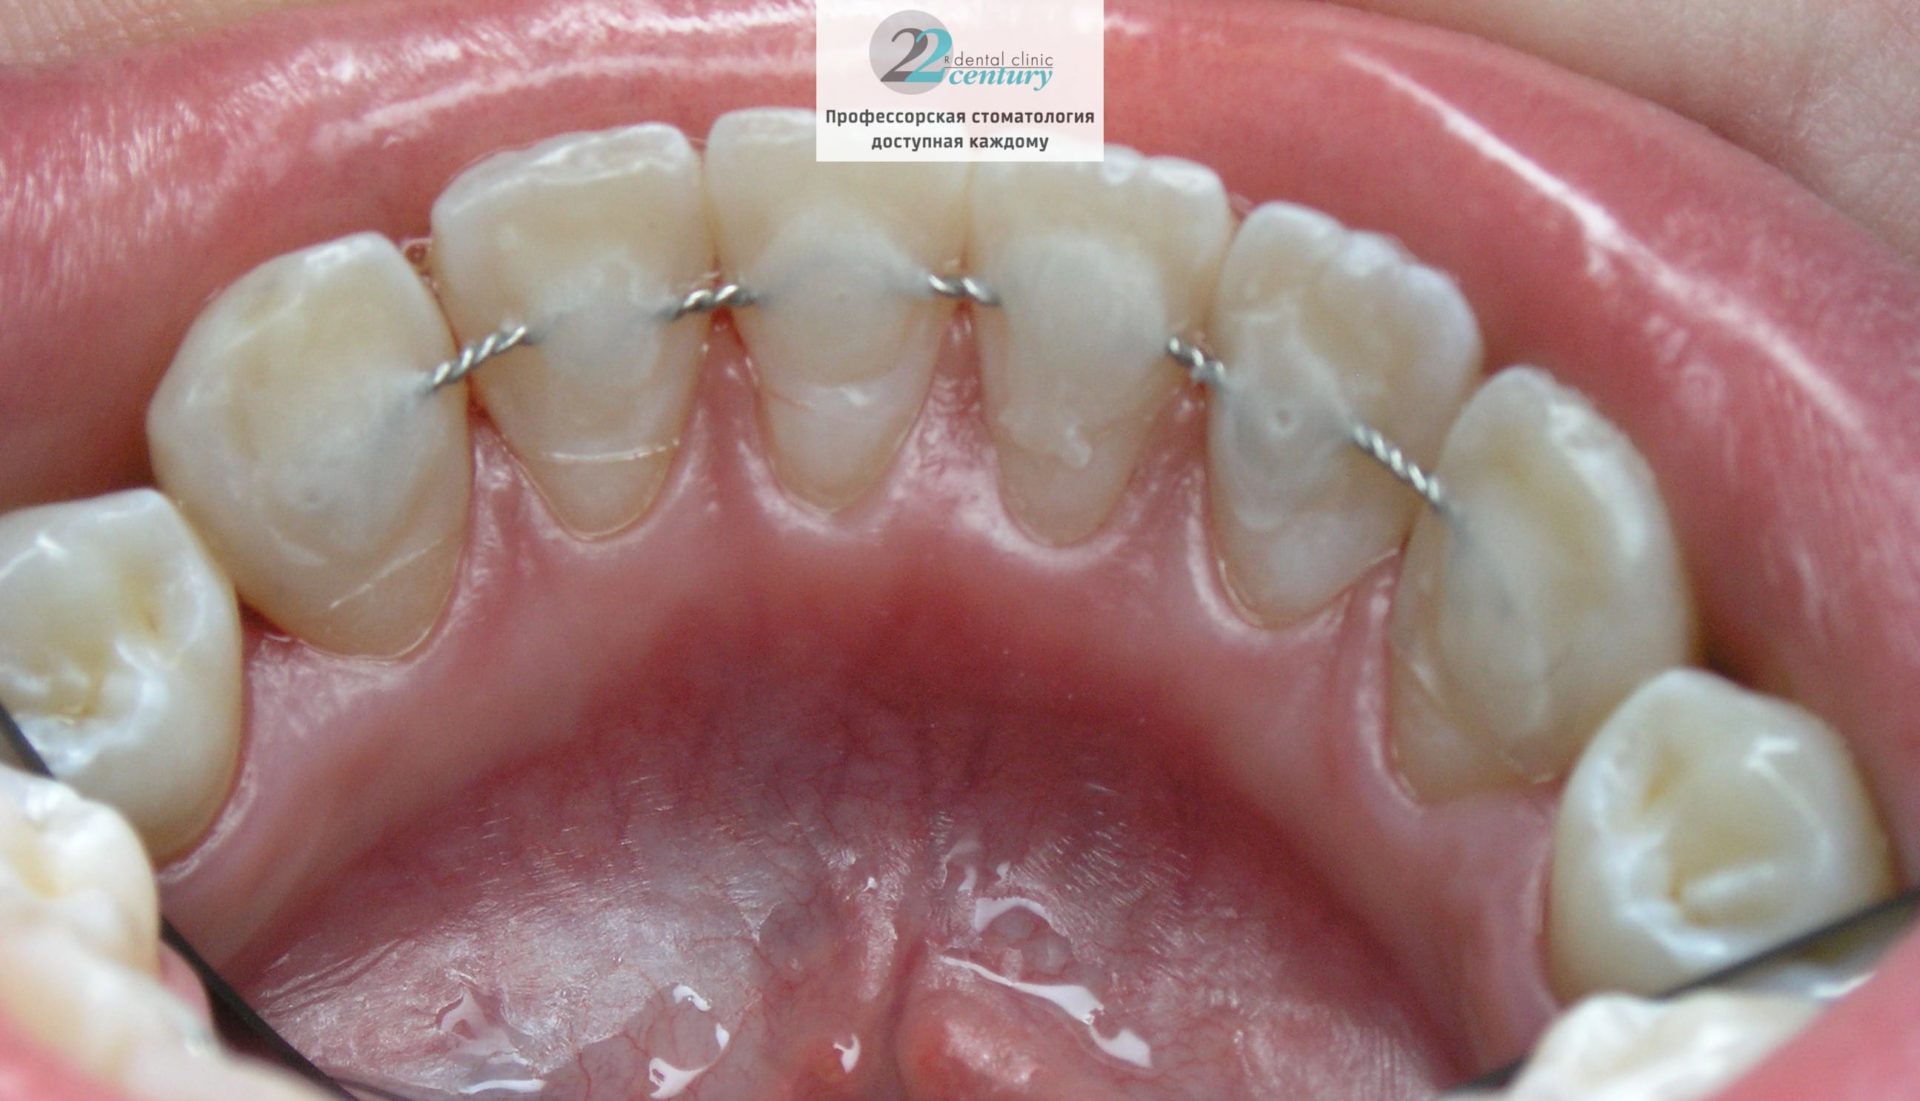

Вантовое шинирование зубов в современной стоматологии – это стягивание зубов крепкой тонкой нитью, которая позволяет осуществить прочную горизонтальную связь между соседними зубами. Эта процедура не вызывает у пациента дискомфорта или ощущения стянутости – она достаточно естественна и физиологична.

Для осуществления процедуры шинирования зубов в предварительно подготовленные бороздки на зубах (немного выше десны) размещается арамидная нить, которая затем “закрывается” светоотверждаемым композитом, подобранным под оттенок эмали. Таким образом, для окружающих следы шинирования оказываются незаметными.

Шинирование может быть выполнено стекловолокном – такие шины адгезионные композитные армированные стекловолокном, которое биоинертно, имеет высокий модуль упругости, химически соединяется с композитом, не набухает, имеет высокие эстетические показатели.